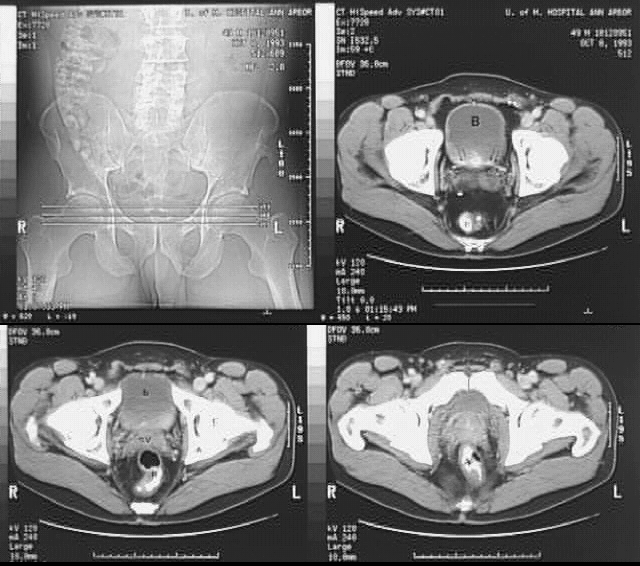

Radiology Images

Pelvis & Perineum: Pelvis CT: